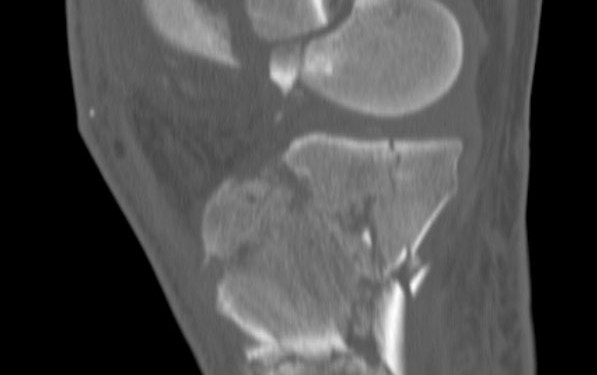

Ekstremite Kırıkları diz parçalı kırığı

diz parçalı kırığı (femur distal ve proksimal tibia)